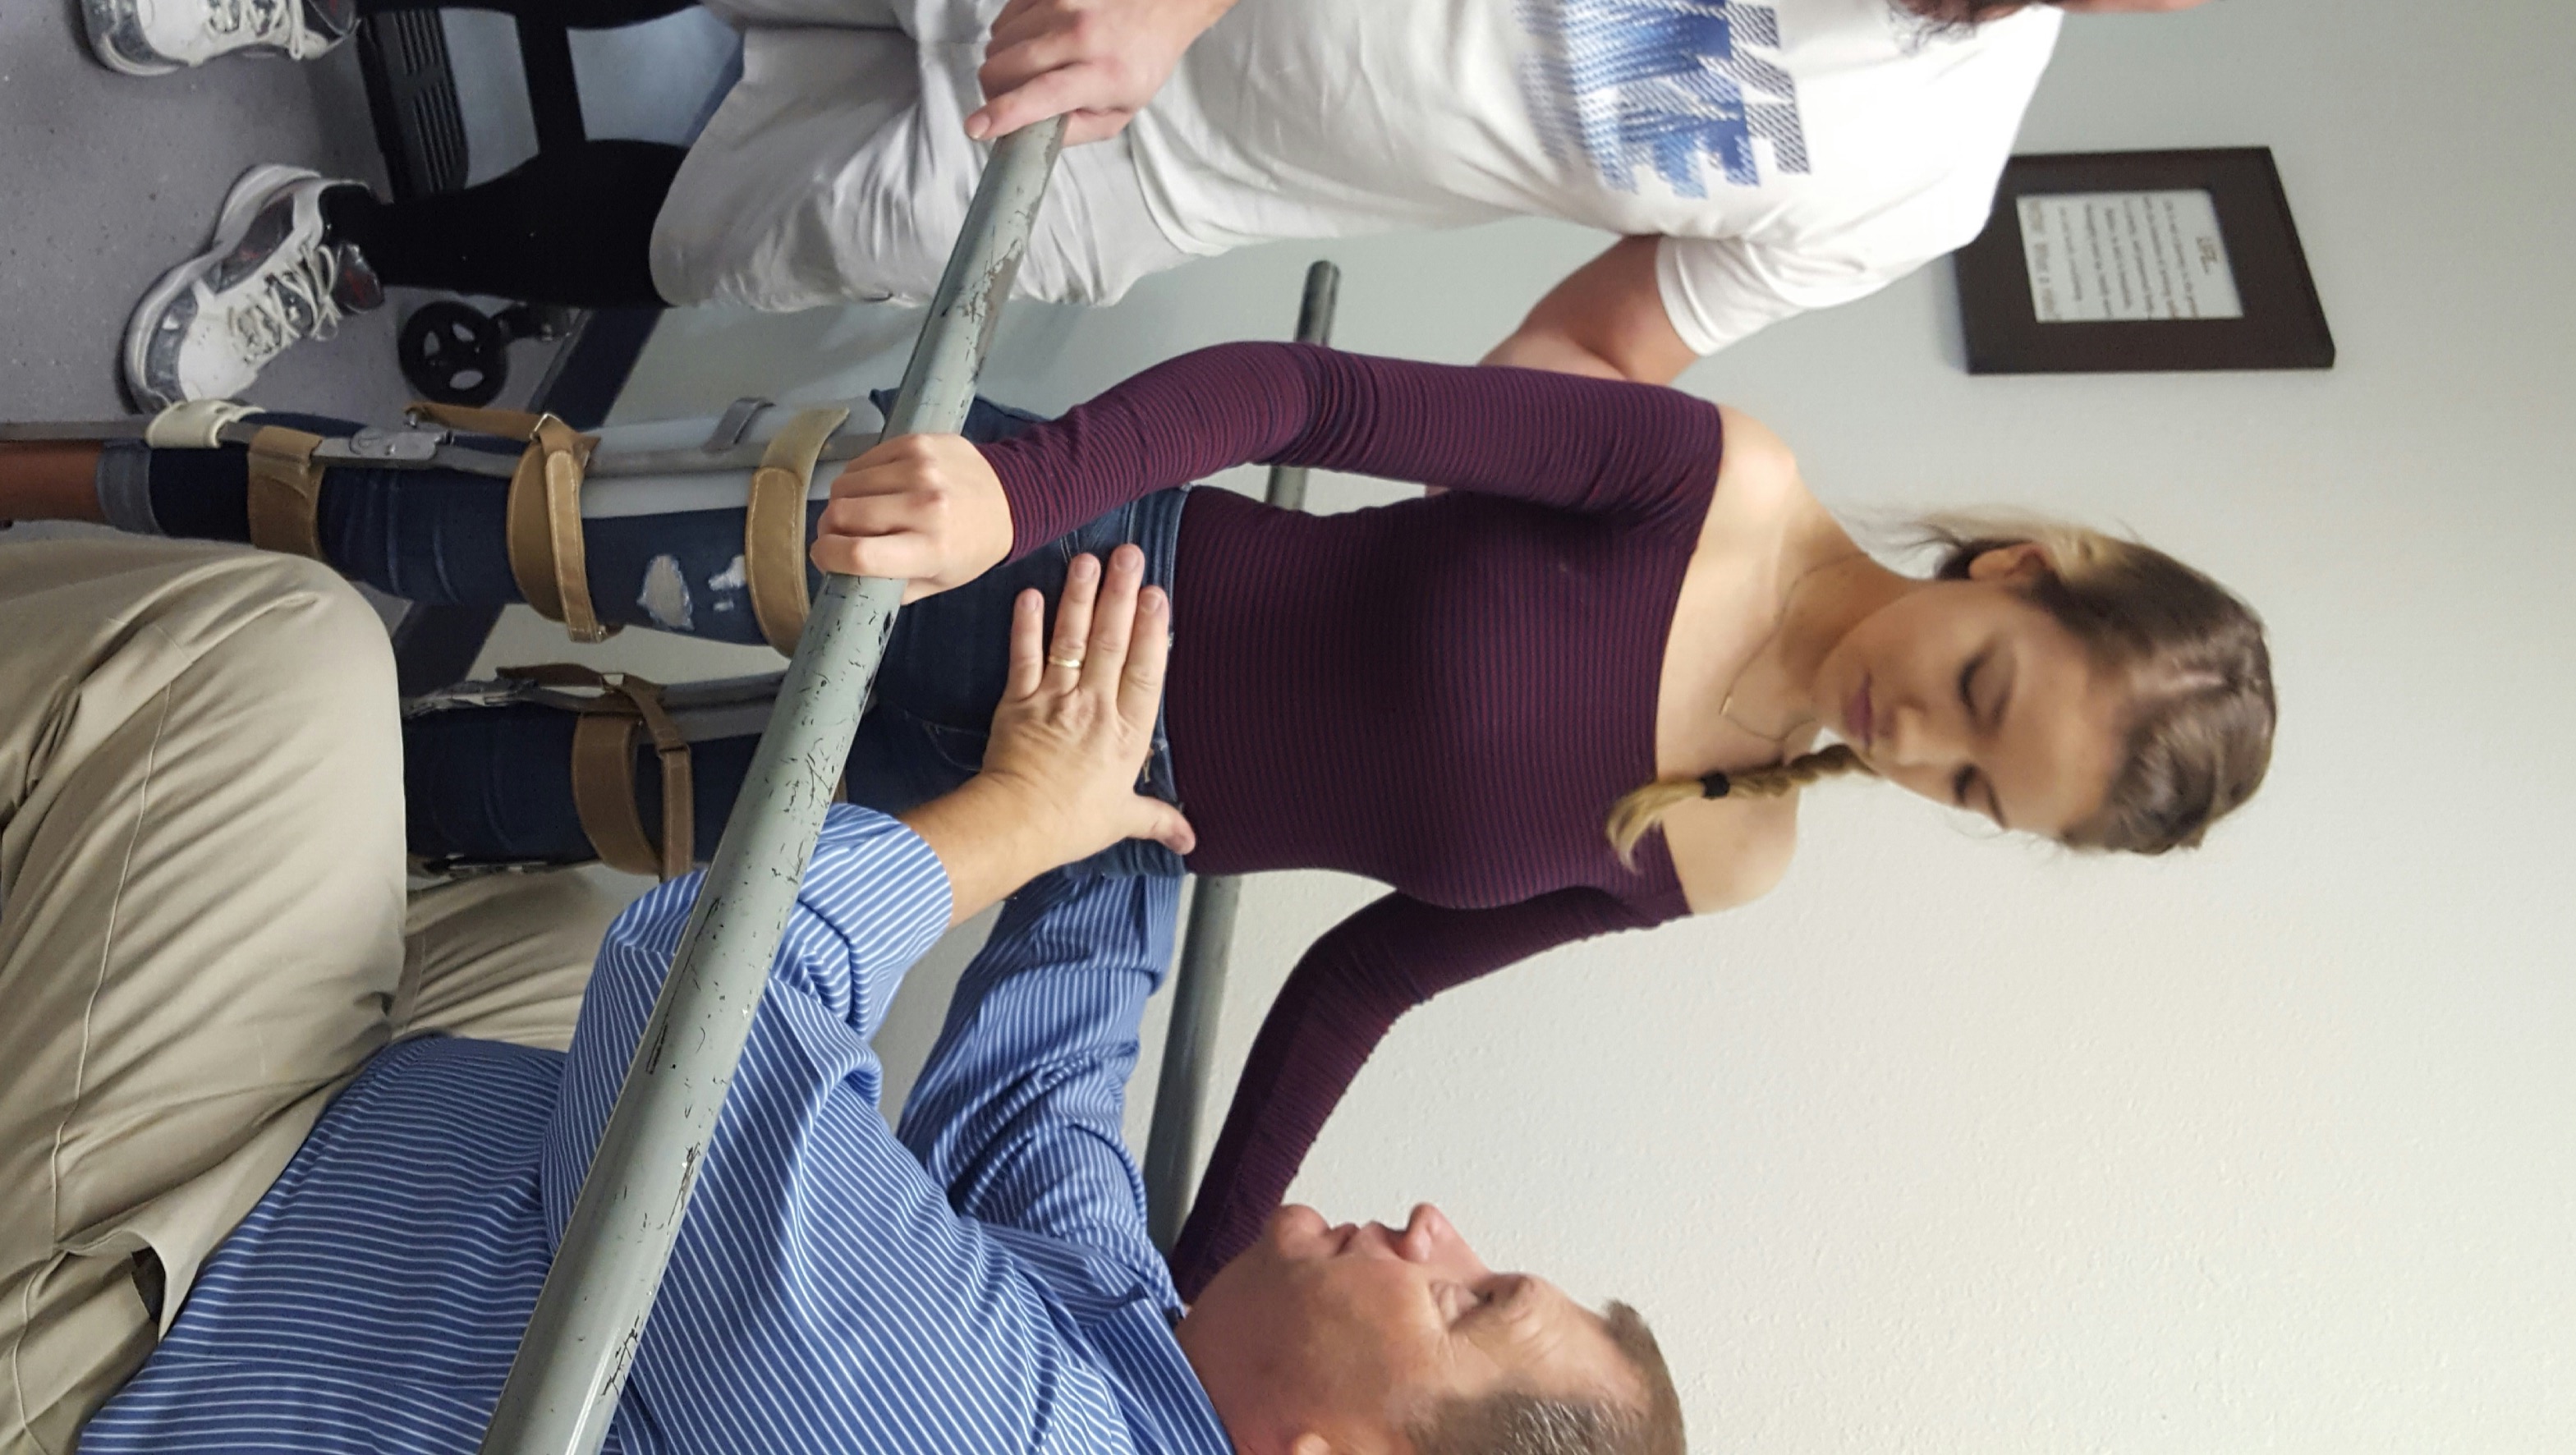

Lauren suffered a T-9 complete spinal cord injury from a car accident in 2015. This life changing injury is followed by a long journey of physical therapy to relearn how to walk and to keep the body healthy. The intense physical therapy required for SCI’s is unfortunately not covered by insurance so it is hard to continue consistently without assistance. Any amount helps and is appreciated <3 thank you for following on this journey